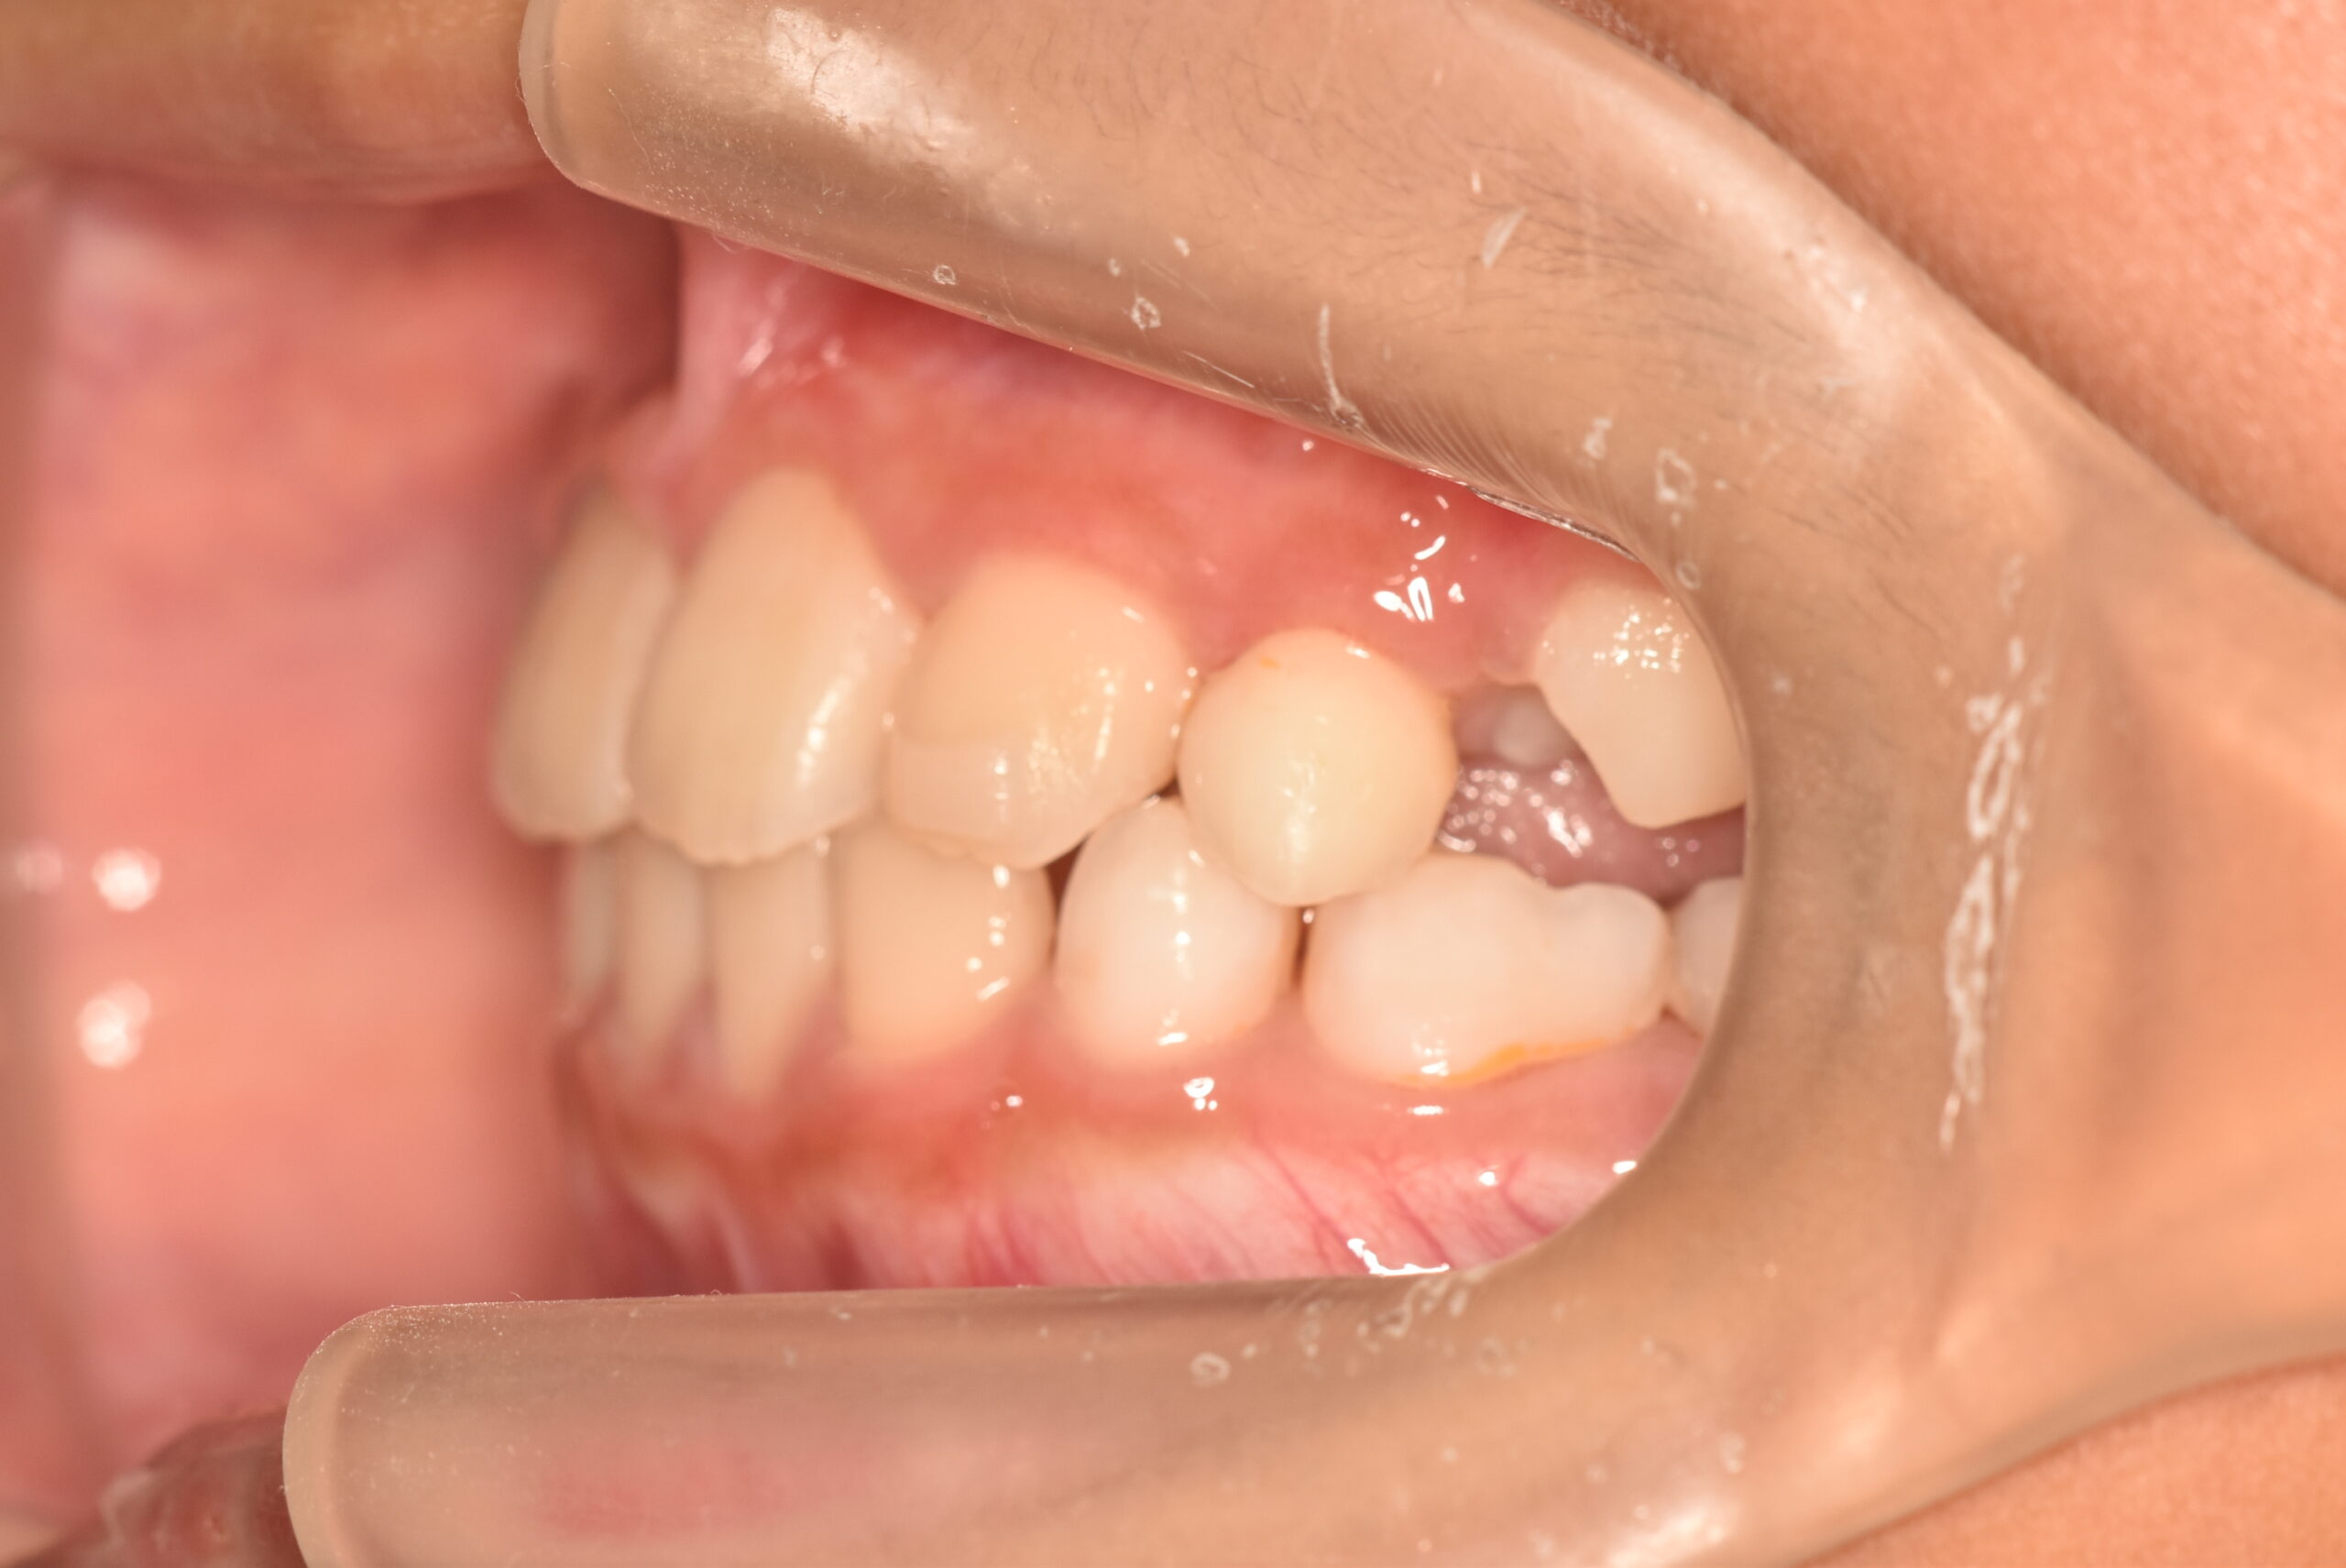

| 治療内容の詳細 | 初診時9歳3ヶ月の男児で、前歯が磨きにくく虫歯になりやすいことを気にされ来院されました。 検査の結果、前歯部叢生を伴うアングルⅠ級不正咬合と診断しました。 治療としてはマウスピース矯正(インビザラインファースト)で配列を行い、上下顎の側方拡大により永久歯の萌出スペースを確保しました。 治療期間は、1年6ヶ月でした。 今後、永久歯(側方歯)の生え変わりまで経過観察を行います。 |